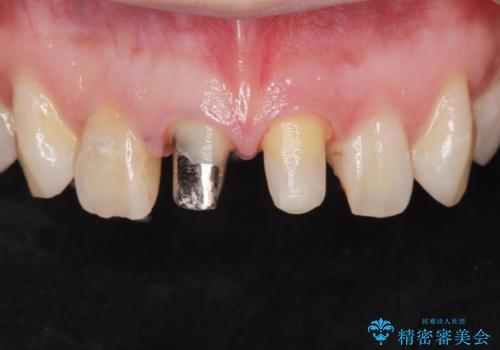

- 前歯のバランスが悪いとの事で来院。

左の前歯は樹脂での治療がされていてう蝕が再発していたので全て取り除き、再根管治療(保険)を行いました。

右の前歯も被せ物を外して左右一緒に作製した方が同じ色で作れるので被せ物のやりかえを行いました。(再根管治療は望まなかった)